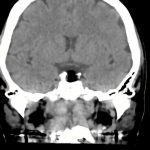

下垂体腫瘍

断層撮影

手術前1

No.’13_143 手術前1

No.’13_143 手術後